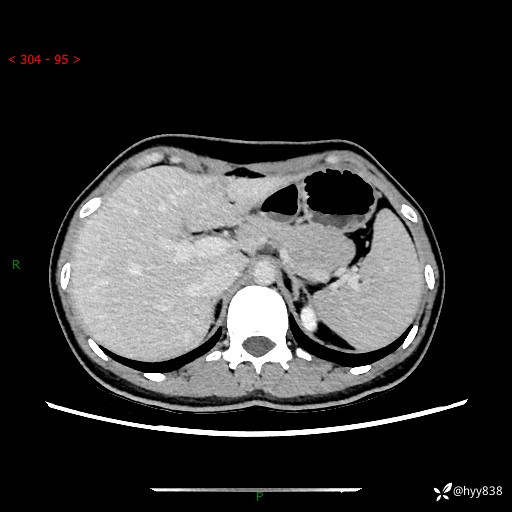

性别:女

年龄:23岁

简要病史:外院发现肝结节,来我院进一步增强确诊

上腹部CT平扫+增强

肝囊肿 (68)